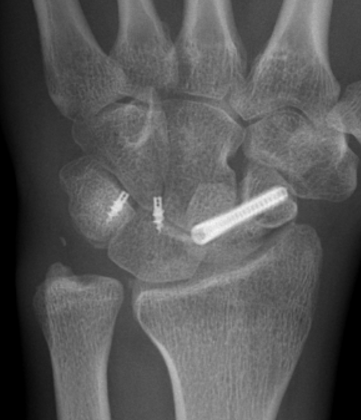

- ORIF scaphoid fracture with headless compression screws

- assess stability of scapho-capitate and scapholunte joint (often ligaments intact and stable)

- K wires lunate-triquetral +/-

- +/- repair LT ligament

- +/- ORIF capitate